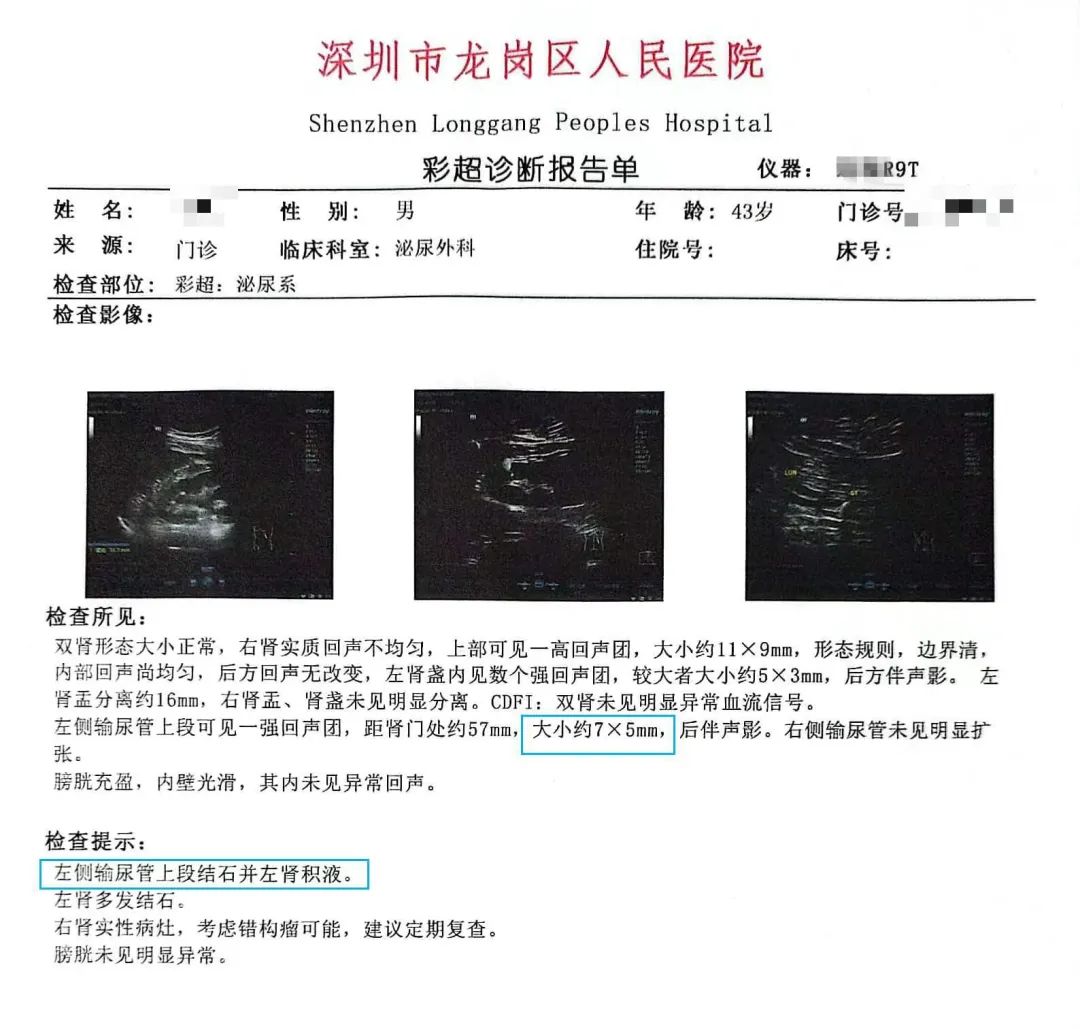

到了医院一做彩超,真相大白:左侧输尿管上段长了个 7 mm*5 mm 大小的结石,左肾还有轻度的积水。

一粒比黄豆还小的结石就能把人折磨得坐立难安,医生宽慰杨先生的紧张焦虑,并且建议杨先生使用体外冲击波碎石术。

①碎石前需完善血常规、尿常规、凝血功能、彩超或泌尿系 CT 等检查。